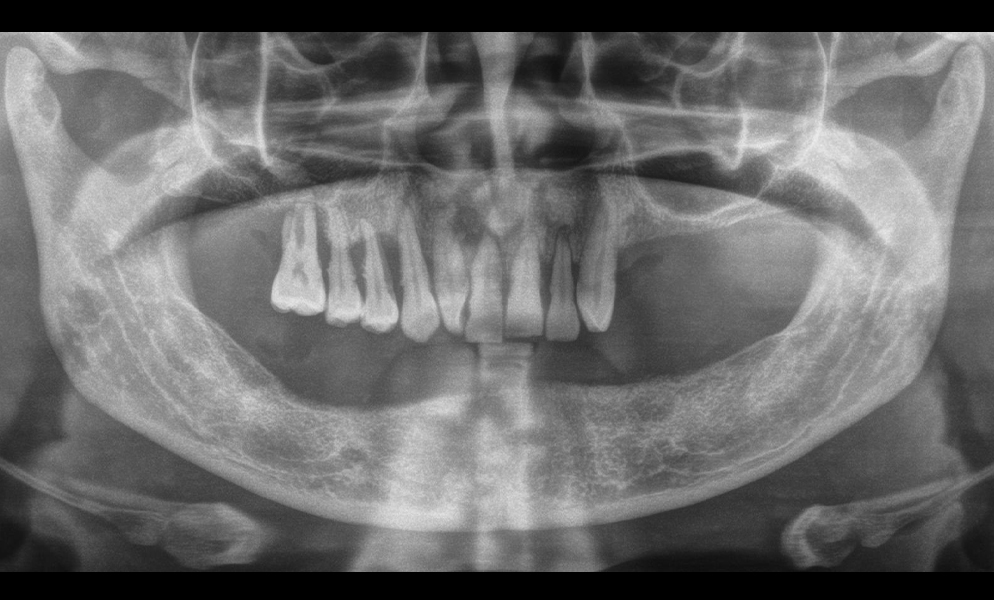

| Before | After |

![]() |

| Fully edentulous lower arch restored with short dental implant (Bicon, USA)-supported prosthesis | |